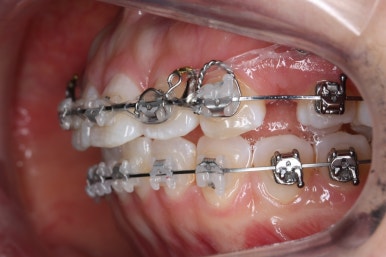

다시 이번 환자분으로 돌아가, 입 안모습을 보시겠습니다.

부산무턱교정 키다리아저씨치과에서 처음 내원하셨을 당시의 입 안의 모습입니다.

아래턱이 작아서 상대적으로 윗니들이 많이 돌출되었고, 뻐드러져 있습니다. 윗니들이 배열되어 있는 형태도 V자에 가깝게 입천장이 좁은 양상입니다.

장치를 부착하였습니다.

이번에 부착한 장치는 엠파워 클리어라고 하는 자가결찰 세라믹장치 입니다.

세라믹이기 때문에 덜 보이며 자가결찰 장치이기 때문에 초기에 가지런해지는 속도가 빠르고 통증이 덜한 장점이 있습니다.

점점 가지런해지고 있습니다.

아래 앞니는 자리가 많이 부족했기 때문에 장치를 제대로 못 붙인 치아가 있고, 자리부터 확보해주고 있습니다.